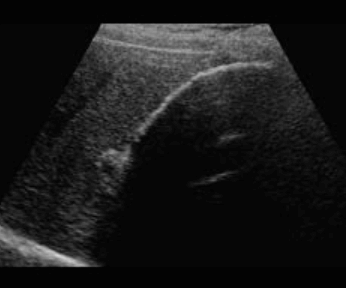

2. Wall thickening (벽비후형)

담낭벽이 국소적 또는 미만적으로 비후 된 암이며 점막하층이 없어 바로 간으로 직접 침윤하여 치사율이 높다. 담낭벽의 불규칙한 비후, 담낭 내강이 뚜렷하지 않으며 담낭벽을 나타내는 선상의 고에코가 뚜렷하지 않다.

벽비후형이 층이 없고, 내강 안 표면이 불규칙일 때, 비대칭적 비후, 담낭벽이 간을 침범할 때, 악성도가 높다.